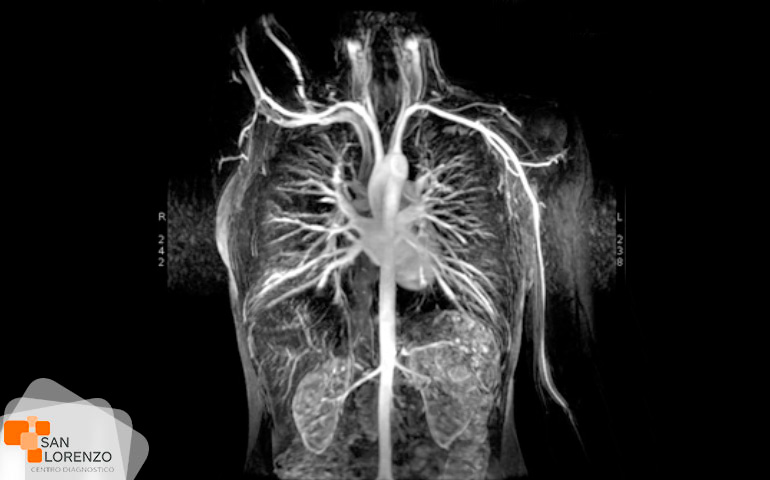

Cuando su médico especialista requiera una mejor visualización de los órganos, o estructuras internas normales o con lesiones, puede solicitar su examen con medio de contraste, éstos son sustancias indispensables para distinguir con mayor claridad áreas del cuerpo o tejidos circundantes que ayuden a diagnosticar condiciones médicas relacionadas con órganos específicos, vasos sanguíneos, o tejidos.

Algunos de los exámenes relacionados con medios de contraste son: Angiotac, Urotac, TAC de abdomen y pelvis, TAC de cerebro en lo que se solicite contraste, y todas aquellas Resonancias magnéticas contrastadas.

¿Para qué tipos de exámenes se aplica la medición de la creatinina? ¿Podemos mencionar los exámenes? Todos los exámenes de RM, TAC que requieran contraste tal como los mencionados anteriormente: Angiotac, Urotac, TAC de abdomen y pelvis, TAC de cerebro en lo que se solicite contraste y todas aquellas Resonancias magnéticas contrastadas.